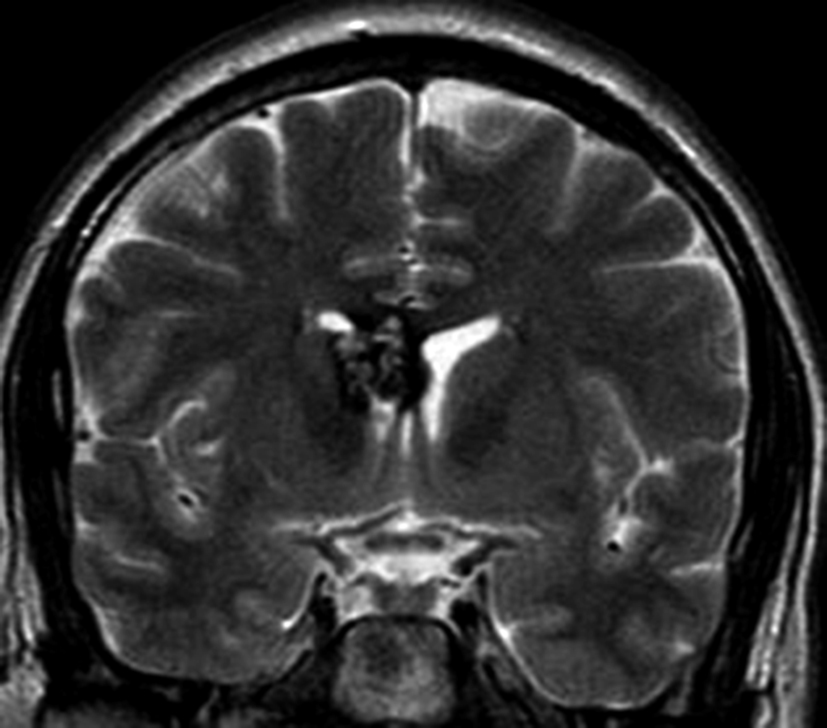

Con los hallazgos tomográficos, no se efectúan planteos diagnósticos y se realiza una resonancia magnética con la finalidad de obtener más datos semiológicos en busca de una aproximación diagnóstica. Se realizó el estudio por medio de secuencias T 1, FSE T 2, FLAIR, SWI y Difusión, en cortes axiales, FSE coronal y sagital T 1. Se realiza la administración de gadolinio DTPA en los tres planos. Se evidencia la lesión bien definida a nivel del ventrículo lateral derecho, que involucra al tronco del cuerpo calloso (Figura 2- C y 3- B). Presenta intensidad de señal heterogénea en secuencias T1 y T2 (Figura 3 y Figura 4). En secuencia ecogradiente se observa una señal marcadamente hipointensa y heterogénea, con un halo hipointenso bien definido (Figura 2- C). No presenta realce significativo tras la administración de Gadolinio (Figura 2- B) y en la secuencia de difusión no presenta restricción.

Figura 4

a y b) Imágenes coronales T2, Ay B. se evidencia la lesión con epicentro en el asta frontal del ventrículo lateral derecho y la extensión al cuero calloso.

La RM es la herramienta diagnóstica de elección. En la RM es una lesión bien definida con intensidad de señal heterogénea en secuencias T1 y T2 resultante de trombosis, fibrosis, calcificación y hemorragia. La metahemoglobina extracelular e intracelular y la trombosis son responsables de la alta señal de intensidad dentro de la lesión, mientras que las calcificaciones, fibrosis y sangre subaguda son responsables de las áreas de baja señal (5). En la secuencia ecogradiente, se evidencia la lesión heterogénea, predominando los sectores hipointensos debido al efecto de susceptibilidad magnética, con un anillo periférico hipointenso que corresponde al depósito de hemosiderina y hierro en el parénquima cerebral circundante. El anillo de hemosiderina puede no ser evidente en el cavernoma intraventricular (1,3,5). El cavernoma es una malformación angiográficamente oculta, debido a su pobre conexión con el sistema vascular y la angiografía cerebral raramente muestra anormalidades (1,3,4,5).